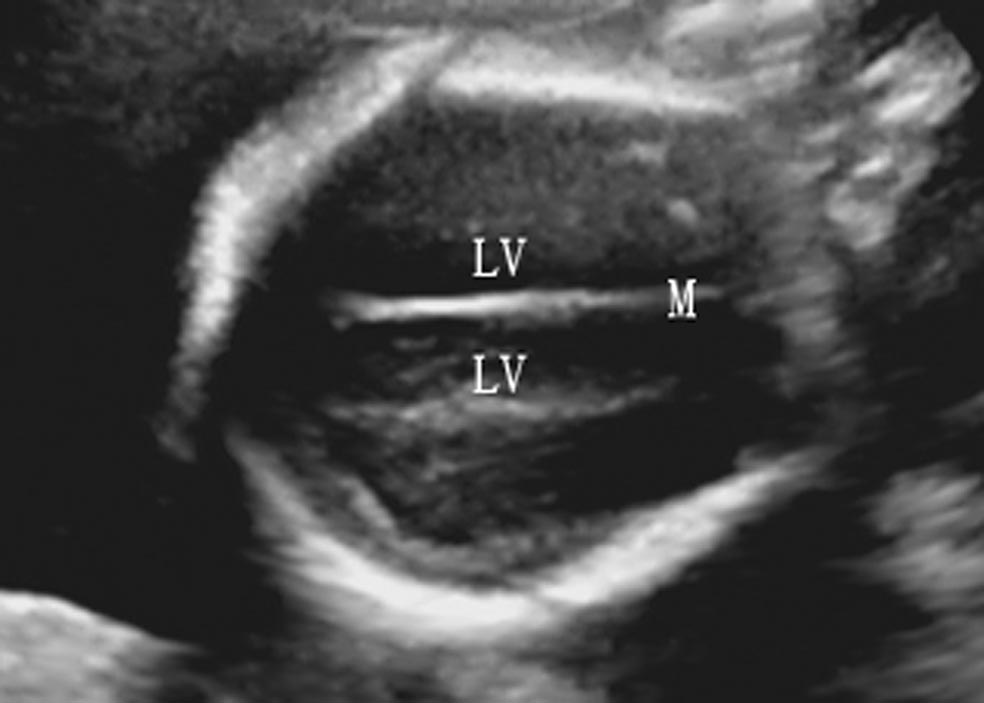

(1)近颅骨顶部横切面:获得TV平面后,声束平面继续向胎儿颅顶方向平行移动,可显示近颅顶部横切面(图7-2),颅骨呈小而类圆形强回声光环,大脑镰和大脑中央裂居中,形成线状强回声的脑中线。中线外侧的无回声为TV顶部,体部外侧的强回声为大脑白质深静脉,引流TV周围白质的静脉血流。

图7-2胎头颅顶横断面声像图